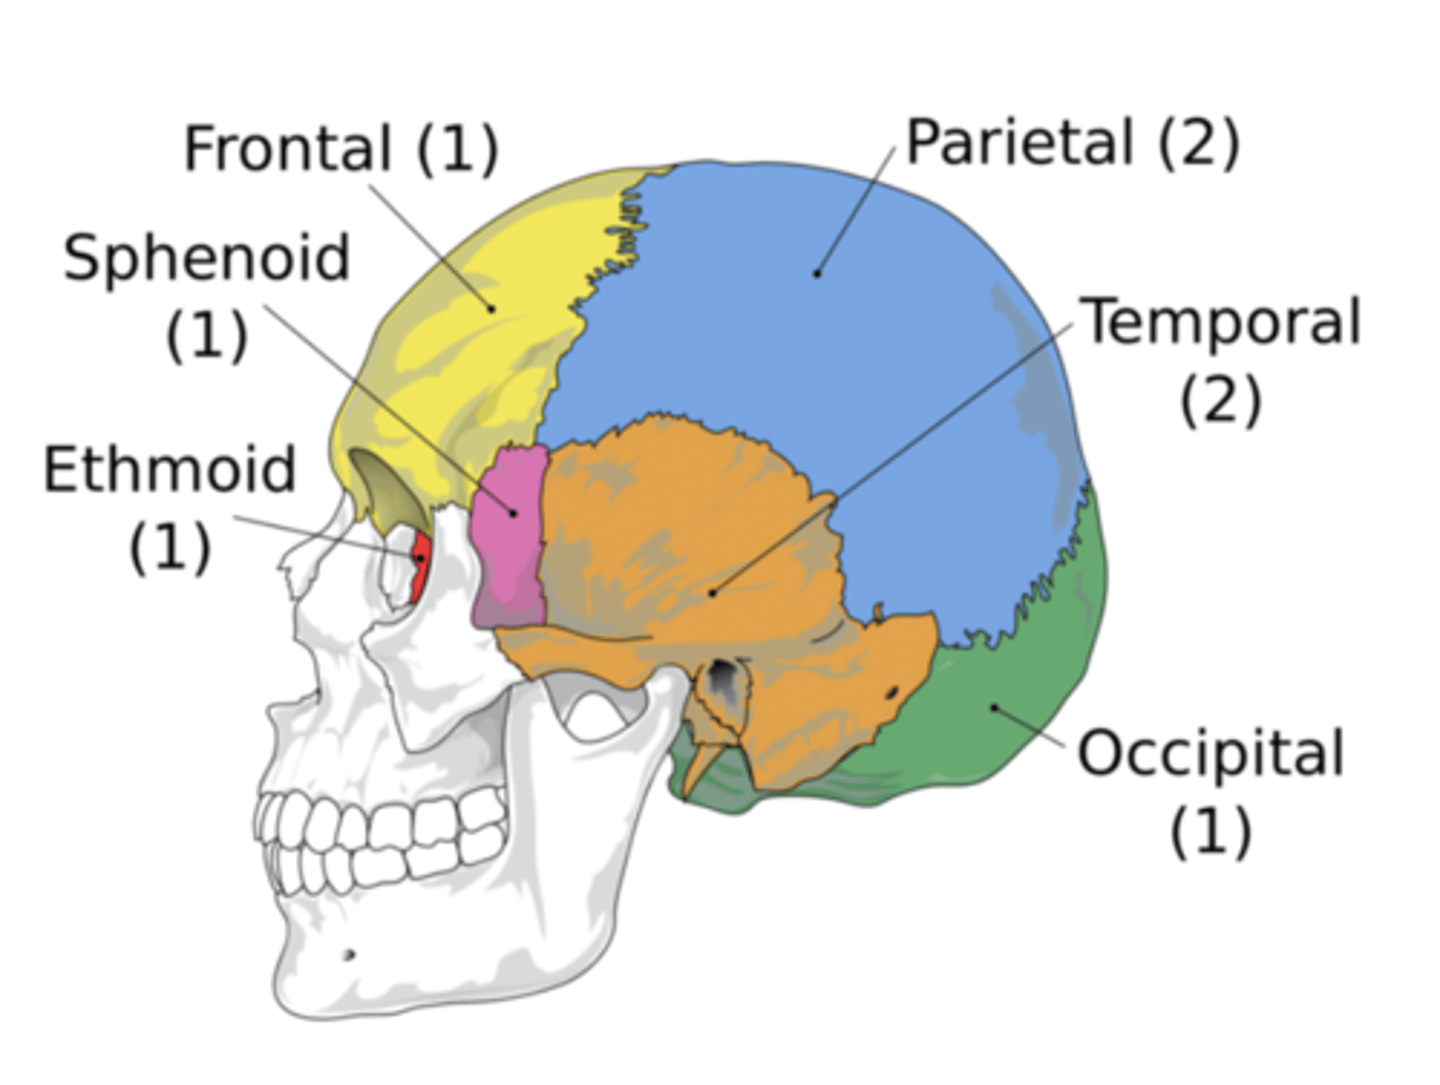

Cranial Bones (8)

- Ethmoid

- Frontal

- Sphenoid

- Temporal (2)

- Occipital

- Parietal (2)

(EFSTOP)

Ethmoid Bone

Forms part of the posterior portion of the nose, the orbit, and the floor of the cranium (red)

Frontal Bone

Bone that forms the forehead (yellow)

Sphenoid Bone

Forms part of the base of the skull and parts of the floor and sides of the orbit (pink)

Temporal Bone (2)

Bone that forms parts of the side of the skull and floor of the cranial activity (orange)

Occipital Bone

Bone that forms the back of the head (green)

Parietal Bone (2)

Either of two skull bones between the frontal and occipital bones and forming the top and sides of the cranium (blue)